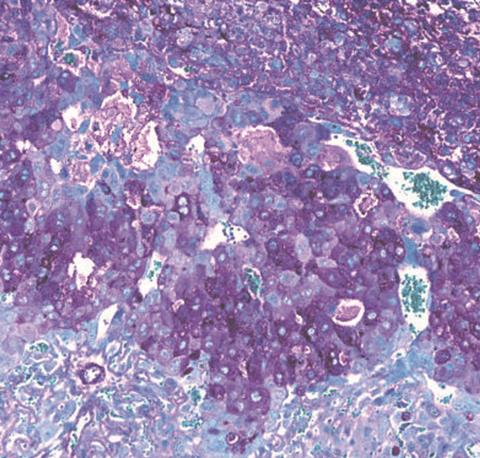

In a study in mice, the researchers compared the placentas of mice with no gut bacteria to those of mice with Bifidobacterium breve in their gut during pregnancy.

In the study, over 150 biological processes in the placenta - involving over 400 different proteins - were found to be different in mice with, and without, Bifidobacterium breve in their gut.

The mice with Bifidobacterium breve in their gut lost fewer of their pregnancies. Their placentas were better at absorbing and transporting nutrients, like amino acids and lactate, from mother to fetus - vital for fetal growth. Their placentas also produced more of the hormones important for pregnancy, such as prolactins and pregnancy-specific glycoproteins.